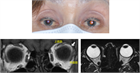

1. 複視とは、見ている物体(対象物)が二つ以上に見える(ダブる)ことで、単眼複視と両眼複視がある。

1. 単眼複視の原因には、乱視、多瞳孔、水晶体亜脱臼、白内障の初期、心因性などがある。

1. 両眼複視には、左右にダブる水平複視、上下にダブる上下複視、傾いてダブって見える回旋複視の3つがある。